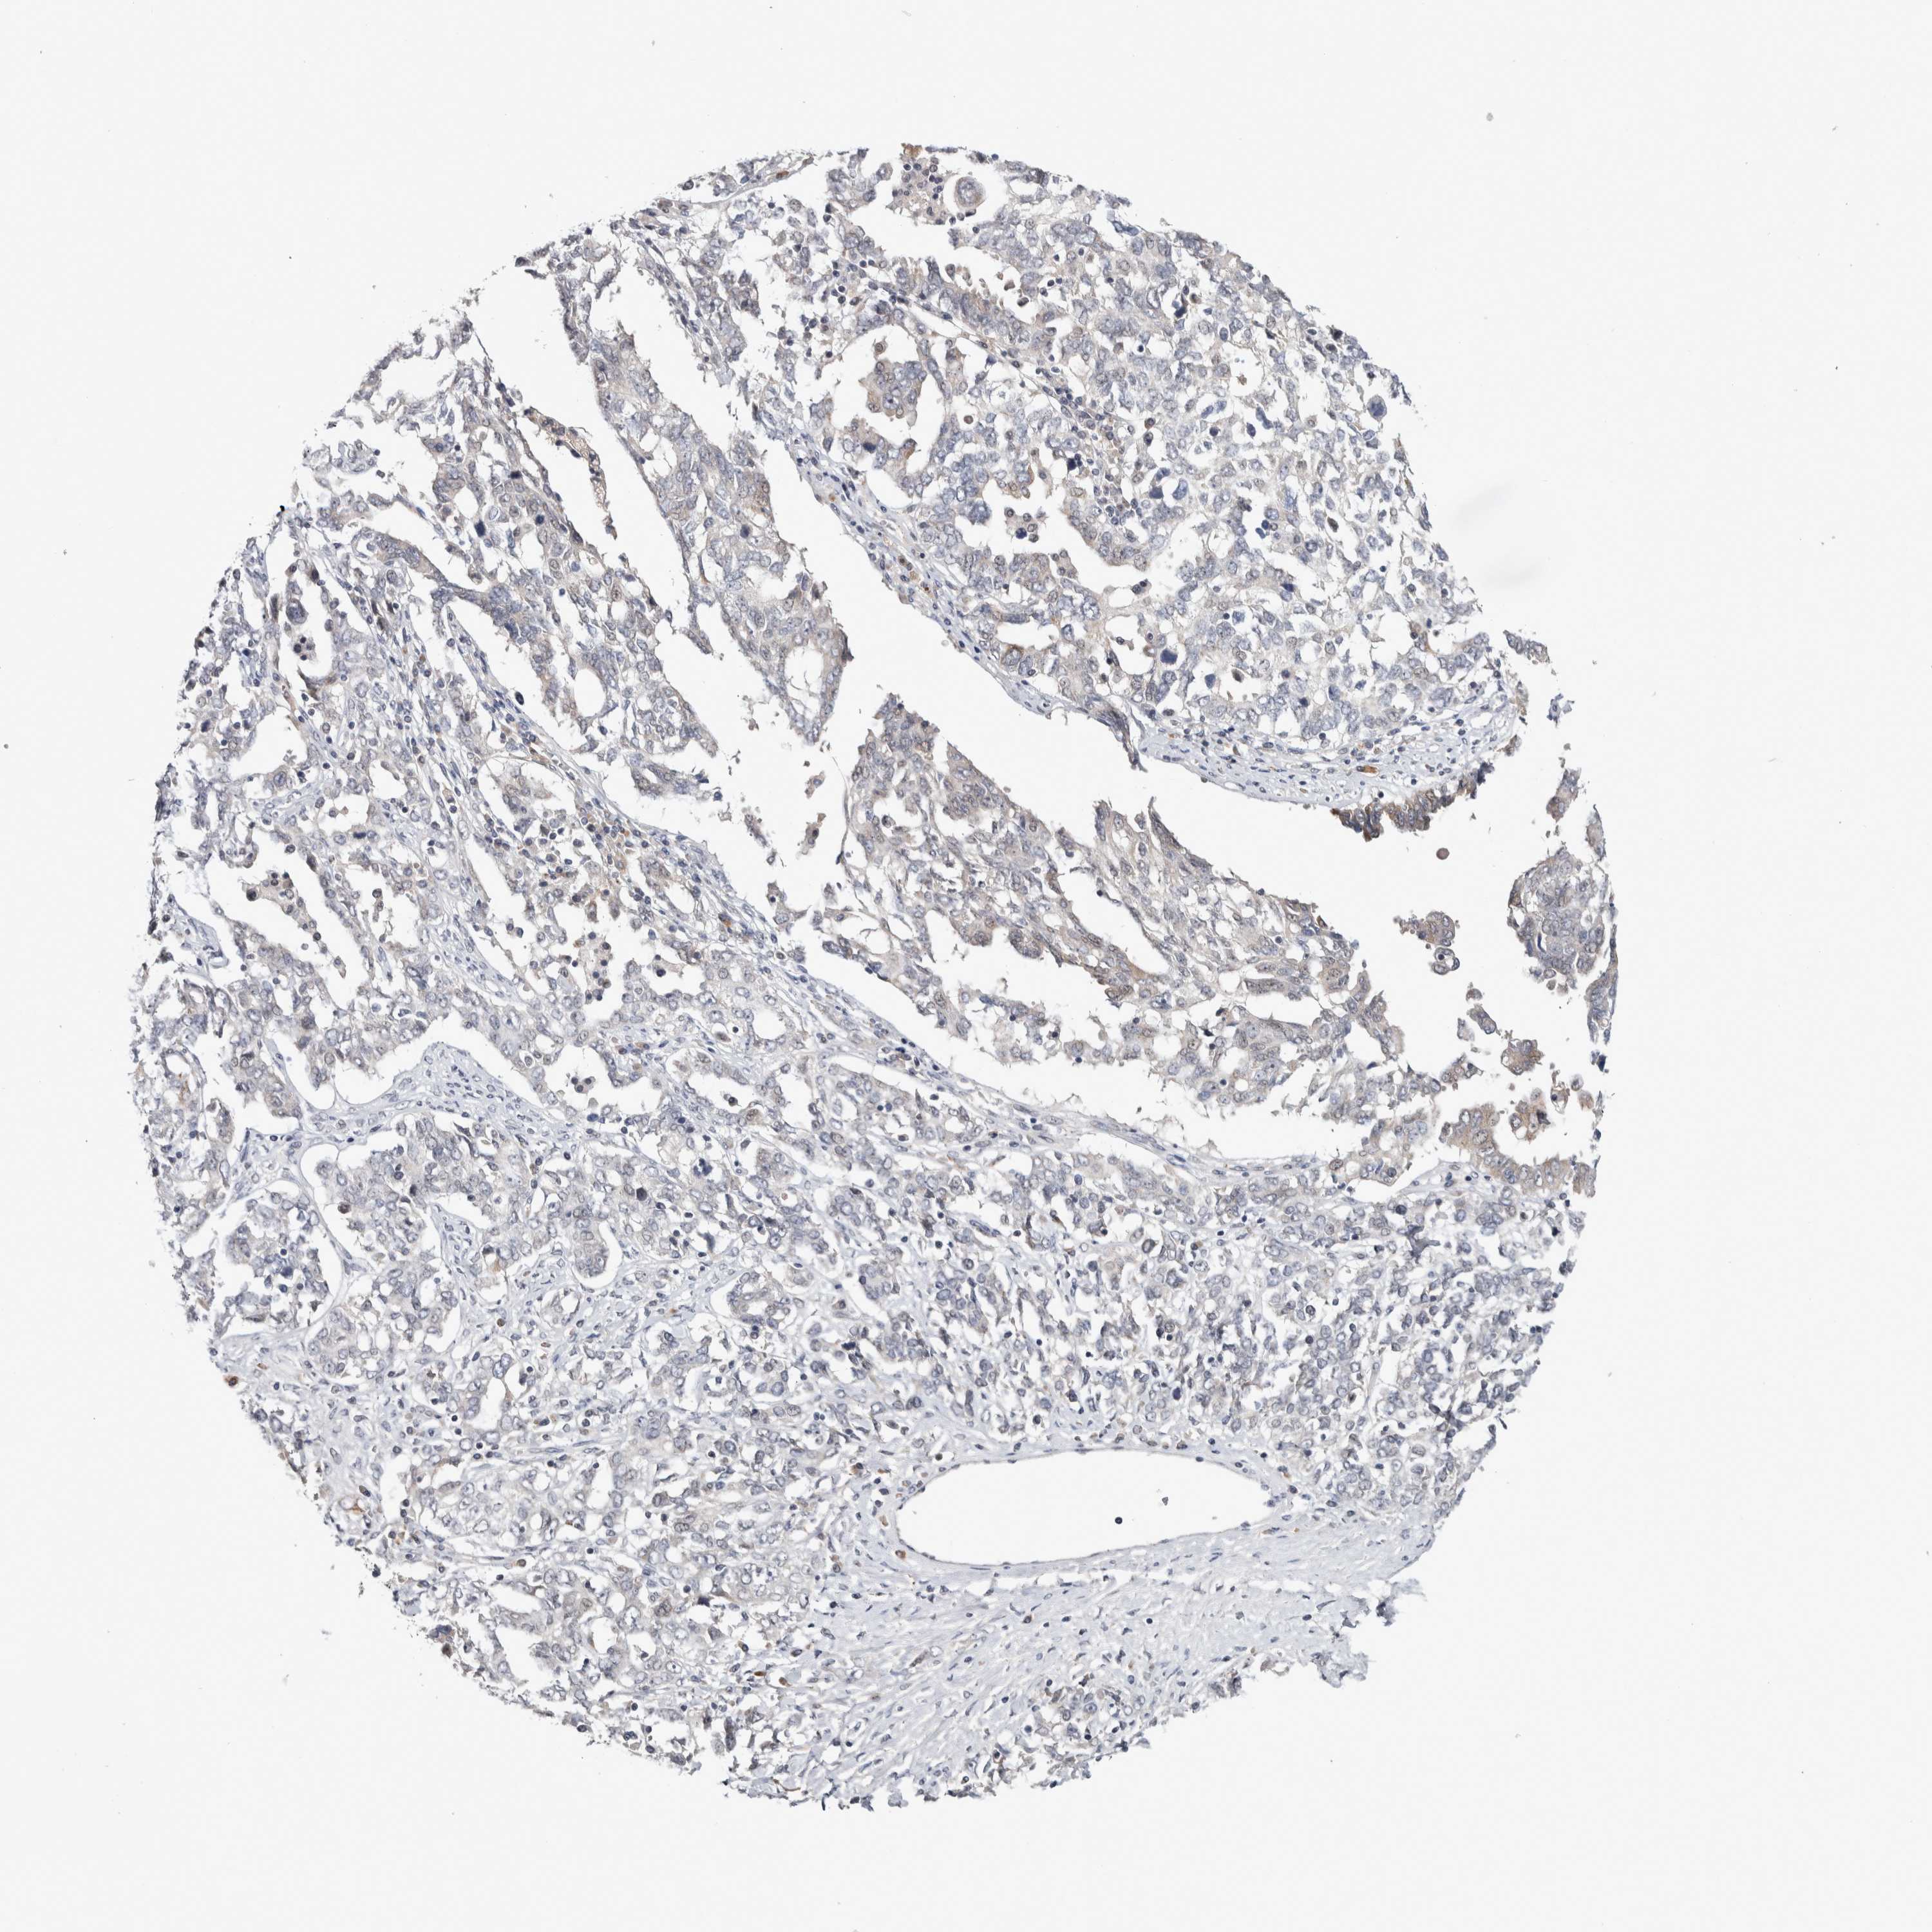

OVARIAN CANCER - Protein expressioni

A mouse-over function shows sample information and annotation data. Click on an image to view it in a full screen mode. Samples can be filtered based on level of antibody staining by selecting one or several of the following categories: high, medium, low and not detected. The assay and annotation is described here.

Note that samples used for immunohistochemistry by the Human Protein Atlas do not correspond to samples in the TCGA dataset.

Antibody stainingi

Antibody staining in the annotated cell types in the current human tissue is reported as not detected, low, medium, or high, based on conventional immunohistochemistry profiling in selected tissues. This score is based on the combination of the staining intensity and fraction of stained cells.

Each image is clickable and will lead to virtual microscopy that enables deeper exploration of all samples and also displays staining intensity scores, fraction scores and subcellular localization as well as patient and tissue information for each sample.

Antibody HPA024230

Carcinoma, endometroid